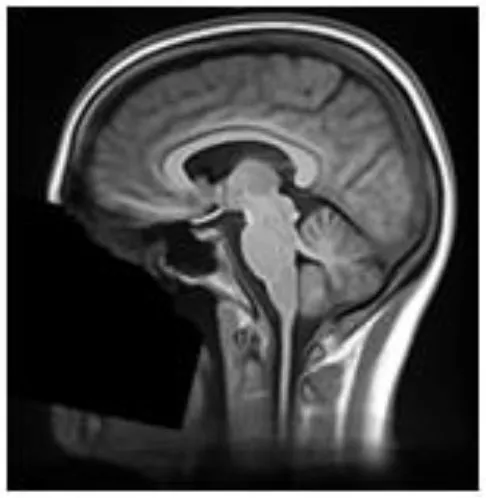

These 68 scans underwent defacing using each of the six defacing algorithms outlined in section Measuring Defacer Success. Following the defacing procedure, each image underwent an additional de-earring step using ear masks generated with fsl_deface (16). For each of the defacing sets, three of the twelve scans from each participant were randomly chosen for the recognition task, for a total test set of 108 defaced images. Two participants were used as “unknowns,” while photographs of the remaining four participants (including the three participants already personally familiar to the raters) were provided to human raters who then attempted to identify the 108 randomly presented defaced images. To help with recognition, each image contained three perspectives of the same 3D render (45° left, straight on, and 45° right of where the face would be; see Figure 1). For each image, raters were instructed to select one of six responses indicating whether they recognized the image as belonging to the person pictured in photograph 1, photograph 2, photograph 3, photograph 4, none of the four photographs, or whether there was not enough information available to make a confident recognition judgment (i.e., “Can't identify”).

FIGURE 1

www.frontiersin.org

Figure 1. True facial recognition task images. Top row: Sample original (pre-defaced) 3D rendered T1 image. Three perspectives of the head were generated, including 45° left, straight on, and 45° right. Bottom: The same image after undergoing defacing (in this case, pydeface) and de-earring. Consent was given by the participant to include their non-defaced MRI render in the publication.